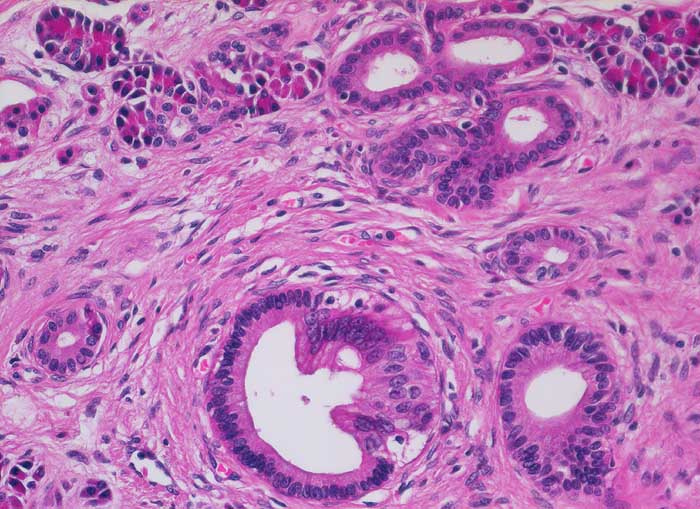

Je nach Ursache der chronischen Pankreatitis unterscheidet sich das Muster der Fibrose. Die Nekrosen des interlobulären Gewebes und der interlobulären Gänge bei ethylischen Pankreatitisschüben führen primär zu einer interlobulären Fibrose und interlobulären Gangstrikturen. In den betroffenen interlobulären Gängen führt der Sekretstau zur Konkrementbildung (verkalkte Proteinpräzipitate). Wie bei einer chronisch obstruktiven Pankreatitis kommt es in den unvollständig drainierten Läppchen zu einer Atrophie der Azini verbunden mit intralobulärer Fibrose. Letztere Areale enthalten schliesslich nur noch Reste unregelmässig verteilter Gänge, Inseln, Nerven und Gefässe. In vielen Fällen lassen sich extrapankreatische Pseudozysten gefüllt mit nekrotisch-hämorrhagischem Detritus in der Nachbarschaft der fibrosierten Bezirke nachweisen. Ein Tumor (> 2066), eine Narbe oder einen Stein können als Folge einer Obstruktion des Pankreasganges im Pankreaskopf eine diffuse Atrophie und Fibrose des Pankreas nach sich ziehen. Diese Form wird als chronische obstruktive Pankreatitis bezeichnet und ist gekennzeichnet durch eine deutliche poststenotische Dilatation des betroffenen Pankreasganges ohne Konkrementbildung und eine diffuse Fibrose des an den obstruierten Gang angrenzenden Parenchyms. Bei einer Schädigung des Gangepithels und der Gangwände wie bei hereditärer oder Autoimmunpankreatitis entwickelt sich primär eine periduktale Fibrose. Im Gegensatz zum duktalen Adenokarzinom ist das erhaltene Parenchym bei der chronischen Pankreatitis lobulär angeordnet. Drüsenepithelien zeigen keine Atypien. Karzinomverdächtig sind irregulär infiltrierende atypische Drüsen, atypische Drüsen in unmittelbarer Nachbarschaft von grösseren Gefässen ohne dazwischenliegende Azini, Perineuralscheideninvasion, rupturierte oder inkomplette Drüsen, und Drüsen mit luminalem nekrotischem Detritus.

• Erhaltene Läppchenarchitektur.

• Breite Bänder von sklerosiertem zellarmem Bindegewebe verlaufen zwischen den Läppchen.

• Atrophie des exokrinen Pankreas.

• Erhaltene Inseln und Gangstrukturen.

• Spärliches chronisches Entzündungsinfiltrat.

• Rechts oben ist eine partiell vom Rand her durch Granulationsgewebe organisierte lytische Fettgewebsnekrose erkennbar. Diese ist Folge eines akuten pankreatitischen Schubs.